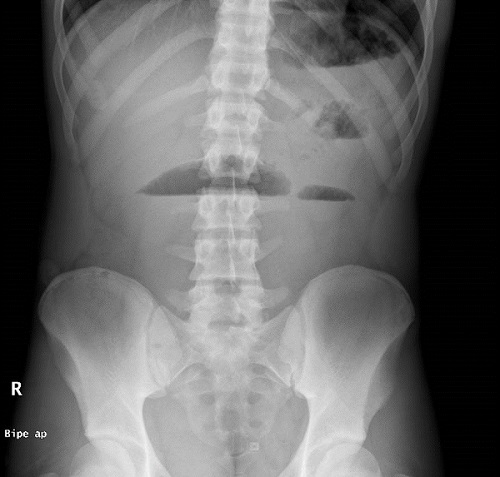

Durante su estancia en urgencias realiza varios vómitos biliosos, que muestran refractariedad a la administración de ondansetrón IV. Además, progresa en intensidad el dolor abdominal y sigue sin emitir heces. Se solicita radiografía de abdomen, donde se observan asas de intestino delgado dilatadas en mesogastrio e hipocondrio izquierdo con material fecal en colon ascendente y presencia de gas distal, imagen sugerente de obstrucción de intestino delgado (Fig. 1). Se realiza ecografía abdominal, donde se confirma cuadro oclusivo/suboclusivo de intestino delgado y se documenta la presencia de contenido mucofecal en íleon distal-terminal (Fig. 2).

Figura 1. Fibrosis quística y síndrome de obstrucción intestinal distal. Asas de intestino delgado dilatadas en mesogastrio e hipocondrio izquierdo, con formación de niveles hidroaéreos

Figura 1. Fibrosis quística y síndrome de obstrucción intestinal distal. Asas de intestino delgado dilatadas en mesogastrio e hipocondrio izquierdo, con formación de niveles hidroaéreos.

El diagnóstico se debe basar fundamentalmente en la historia clínica y en la exploración abdominal5. La radiografía abdominal simple es la prueba complementaria más útil, debido a que si se realiza en bipedestación se pueden apreciar niveles hidroaéreos. Otros hallazgos radiológicos sugerentes de SIOD: materia fecal abundante en el colon, especialmente en la fosa ilíaca derecha, y dilatación de asas de intestino delgado. A veces se identifica el signo de Neuhauser, originalmente descrito para el íleo meconial (imagen “en pompa de jabón”)2.